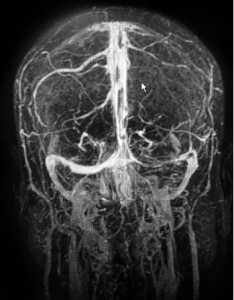

MRI of the 52-year-old female patient with cerebral venous sinus thrombosis.